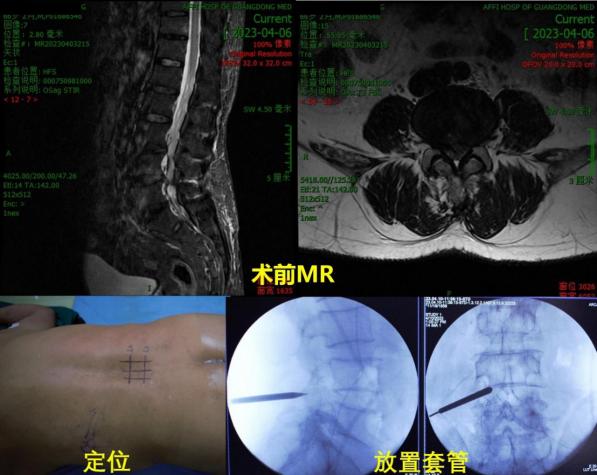

近日,广东医附院脊柱微创外科完成粤西首例双介质脊柱内镜技术(DMSE技术),成功为一名腰4/5椎管狭窄症患者实行双介质脊柱内镜下L4/5单侧入路双侧减压椎间盘髓核摘除术。

副主任孙欣结合该名患者的症状特点、体格检查和影像学资料考虑腰椎椎管狭窄,责任症状节段为腰4/5,并决定采用国内先进的DMSE技术手术治疗

透视下定位,在腰4棘突左侧安装DMSE套管

上图所示:空气介质下视野范围大,水介质下视野更清晰,水压可减少渗血有利于术中操作,可同时完成双侧减压操作